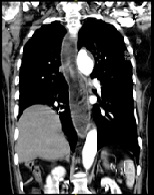

A Combination of Hodgkin's Lymphoma and Tuberculosis occurred with Bilateral Malignant Pleural Effusions

Daniel Valchev*, Mitko Mitev, Evelin Obretenov, Dimitar Kostadinov, Danail Petrov